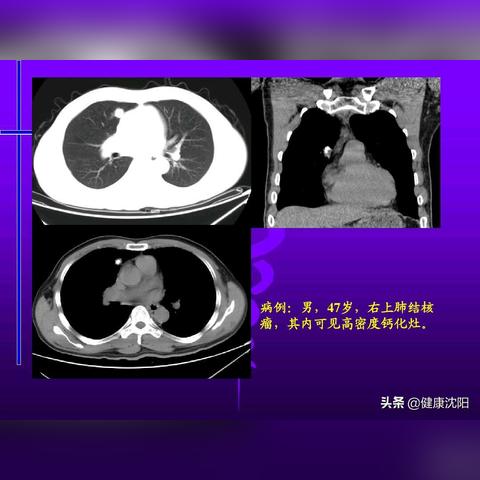

结节性硬化症的临床表现多样,包括皮肤损害、神经系统症状、眼部病变等,最新研究发现,随着疾病的发展,患者的临床表现可能会有所变化,早期诊断对于改善患者预后至关重要。

目前,基因检测和影像学检查是诊断结节性硬化症的主要手段,随着技术的发展,非侵入性的影像学检查如MRI和PET在诊断中的应用越来越广泛,生物标志物的研究也在不断深入,有助于早期诊断和病情监测。